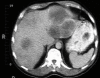

Case presentation: A 65-year-old Caucasian woman with lethargy, loss of appetite and peripheral edema was found to have anterior hypopituitarism. Magnetic resonance imaging showed no mass lesions in the pituitary although a positron emission tomography scan showed abnormal pituitary activity. An abdominal computed tomography scan revealed multiple intra-abdominal lymph nodes, which on histology proved diagnostic of diffuse large B-cell non Hodgkin's lymphoma. She received six cycles of R-CHOP chemotherapy, after which she achieved a complete metabolic response at all known previous sites of the disease, confirmed by positron emission tomography scanning. Concomitant with the tumor response, there was full recovery of adrenal, thyroid and gonadal axes which has persisted at 10 months follow-up.